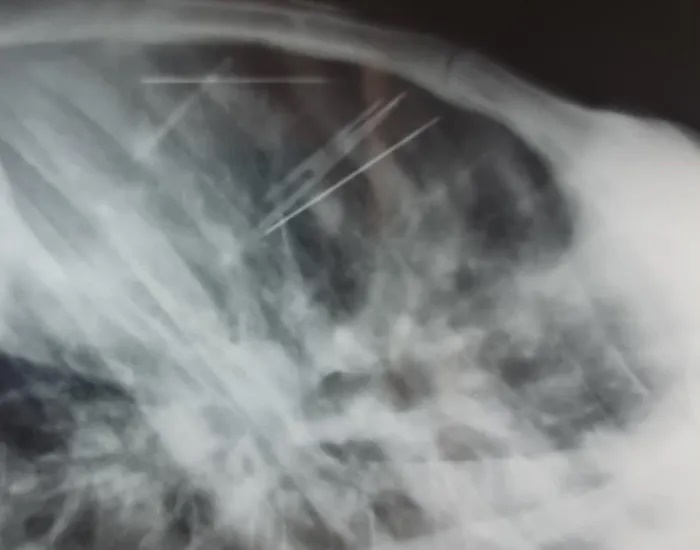

Những chiếc kim bệnh nhân tự đâm vào lồng ngực - Ảnh: Bệnh viện ĐKTPCT.

Tiếp nhận bệnh nhân, các bác sĩ tiến hành chụp X-Quang và CT-Scan lồng ngực thì bất ngờ phát hiện có 7 dị vật hình dạng như chiếc kim khâu dài khoảng 4cm nằm ở trung thất và khoang màng phổi trái của bệnh nhân, kèm theo đó là tràn dịch màng tim lượng vừa.